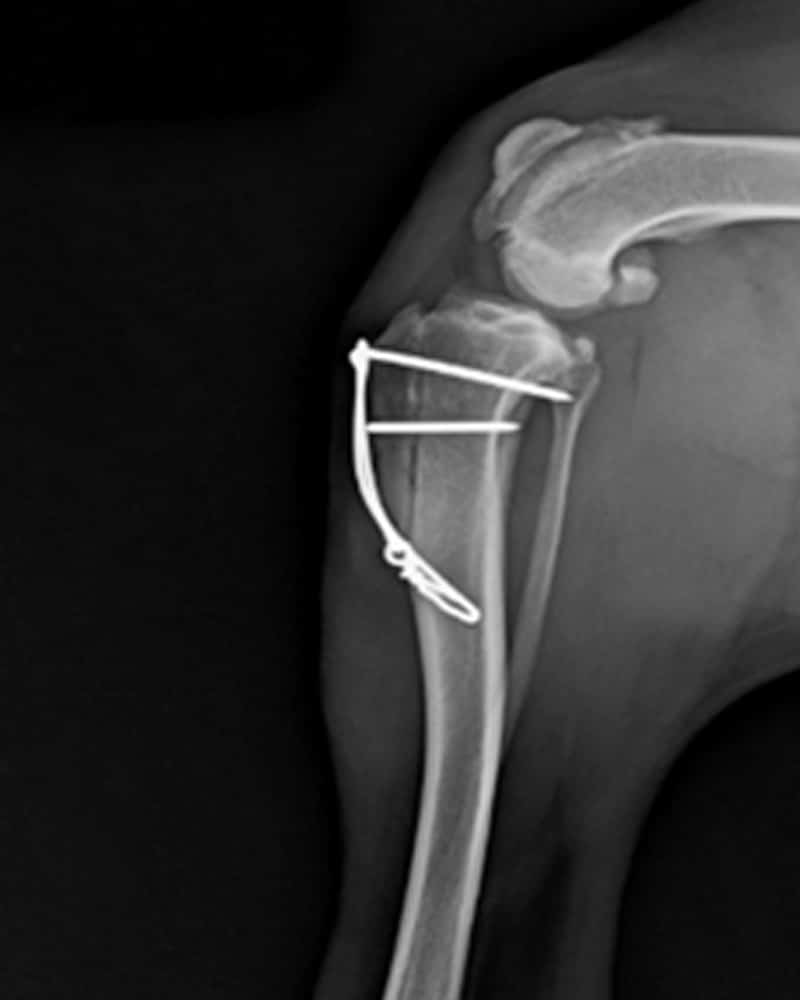

A Tibial Plateau Leveling Osteotomy is performed to treat cranial cruciate ligament (CCL) tears, one of the most common orthopedic injuries in dogs. Rather than repairing the ligament directly, this surgery changes the angle of the tibial plateau (the top of the shinbone) to stabilize the knee and prevent abnormal forward motion. Our doctors will examine your pet and discuss whether TPLO surgery is the most appropriate option. Tibial Plateau Leveling Osteotomy (TPLO)